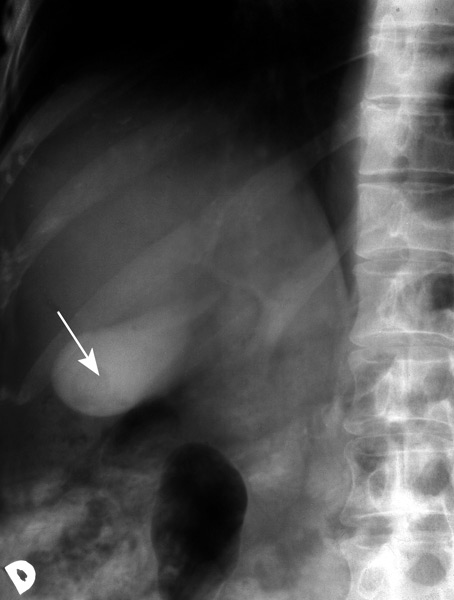

KOLECISTOGRAFIJA, u dnu žučnog mjehura ispunjena kontrastom nalazi se okrugla sjena žučnog kamenca (strjelica)

kolecistografija (grč. χολή: žuč + cisto- + -grafija), radiološka metoda prikazivanja žučnoga mjehura posebnim kontrastnim sredstvom koje se, uzeto na usta, nakupi u žučnome mjehuru nakon 12 do 14 sati. Kako u nakupljanju kontrastnoga sredstva sudjeluju mnogobrojni čimbenici, ta metoda nije jednako pouzdana kao kolangiokolecistografija, gdje se kontrastno sredstvo ubrizgava intravenskom injekcijom ili infuzijom; rendgensko se snimanje obavlja nakon 30, 60 i 120 min, pa se analiziraju žučni vodovi i žučni mjehur.